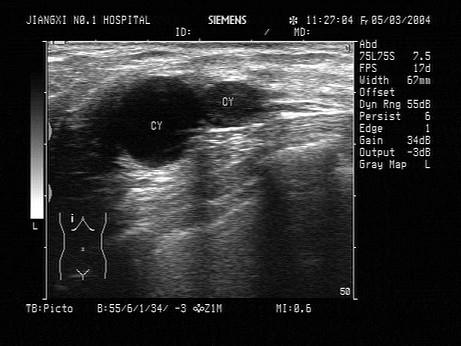

问题 患者,女性,超声见乳房内无回光团,边清壁薄,CDFI未见血流,如图所示考虑为?(?)

选项 A.乳腺癌 B.乳腺腺瘤 C.乳腺脓肿 D.乳腺囊肿 E.以上都不是

答案 D